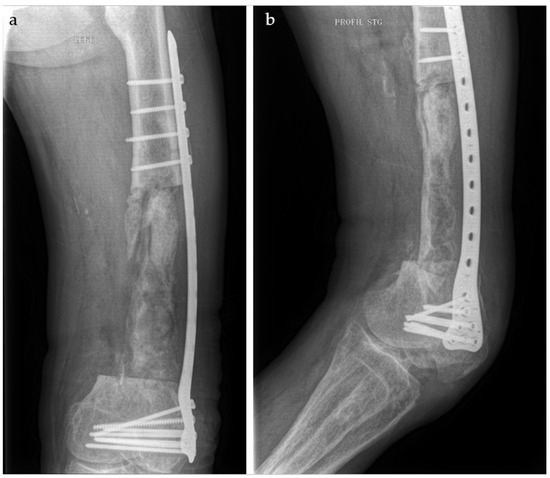

The Use of the Masquelet Technique in the Treatment of Pathological Distal Third Femoral Fracture Secondary to Chronic Osteomyelitis

2. Case Report